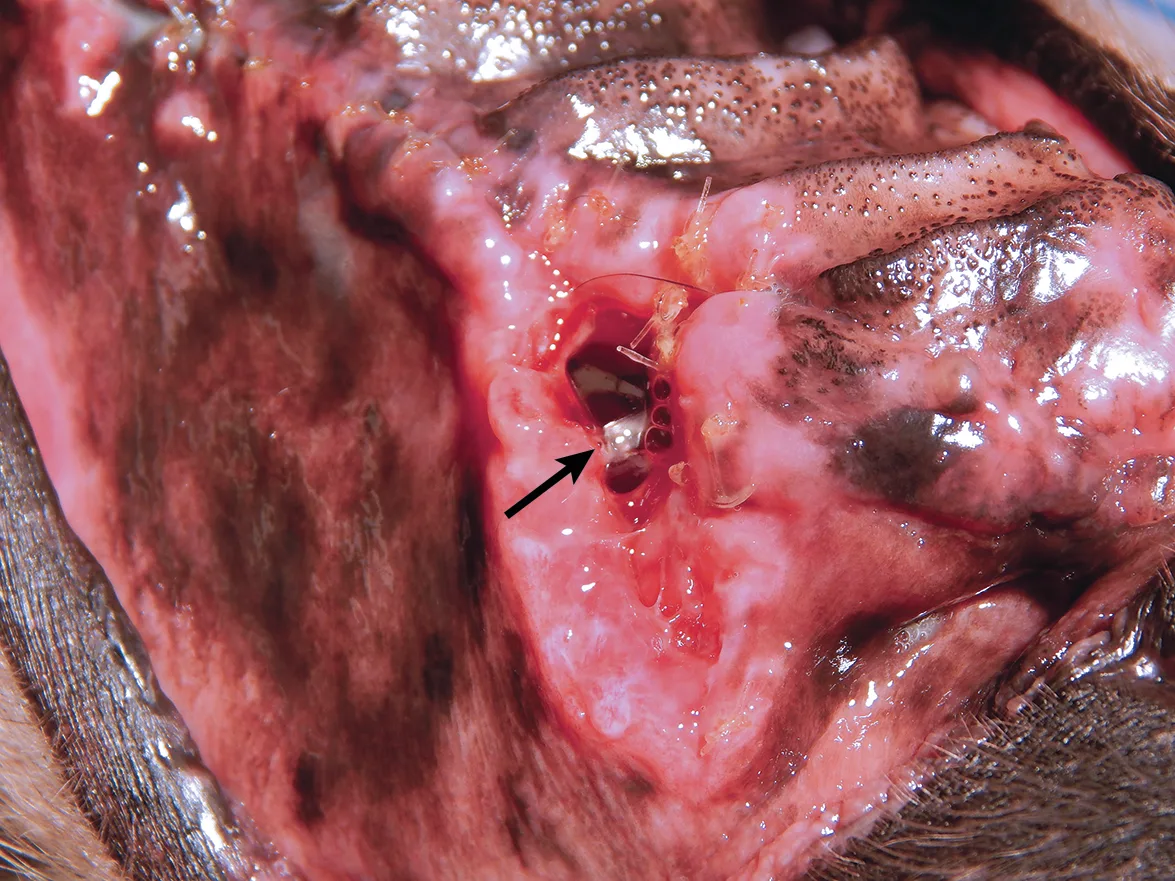

Most tooth extractions and many periodontal treatments require elevation of mucogingival flaps for appropriate removal of buccal alveolar bone. Gingival flap dehiscence (Figure 1) is the most common complication of dental extractions and often occurs with other types of maxillofacial surgery.3 Dehiscence is more common when gingival tissue is damaged by aggressive tissue handling during surgery or when a gingival flap is closed under tension.

(A) A dog with a large area of dehiscence associated with left maxillary canine tooth extraction; a large oronasal fistula is visible with yellow foreign material present in the nasal cavity (arrow). (B) A dog with a small area of dehiscence associated with left maxillary canine tooth extraction; an oronasal fistula is visible in the center of the extraction site closure (arrow).